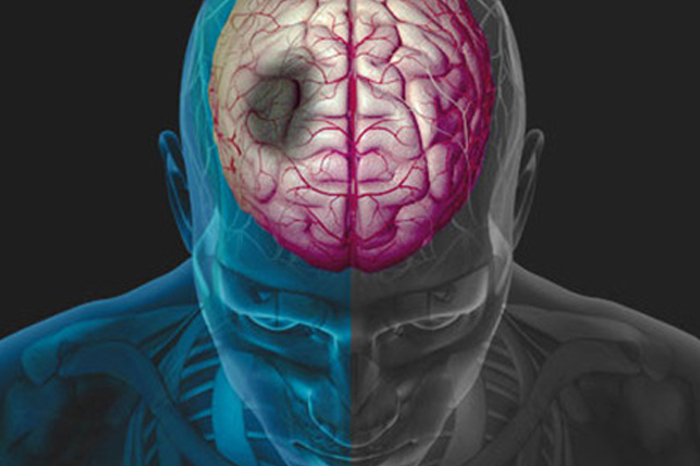

El infarto cerebral, también conocido como enfermedad cerebral vascular o embolia, sucede cuando se forma un coágulo en alguna arteria del cerebro, lo que implica que la arteria se obstruya y no haya flujo sanguíneo y con ello falta de oxigenación.